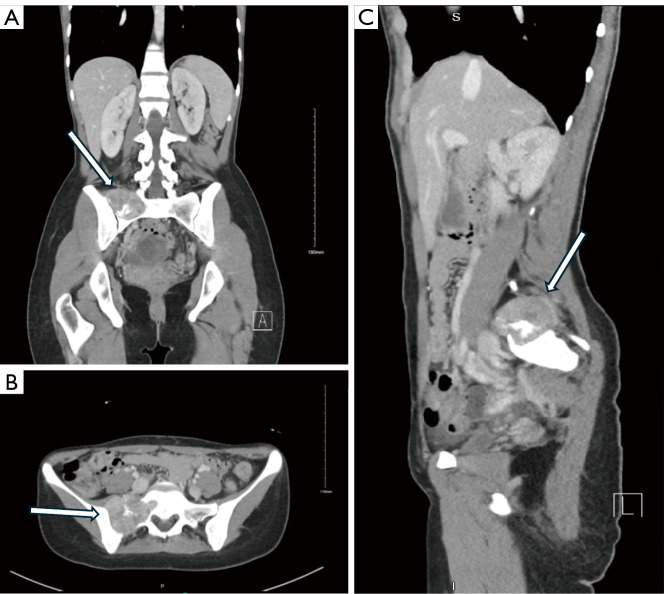

Case description: A 23-year-old female known case of ovarian cyst presented with a two-year history of low back pain and constitutional symptoms. Pelvic magnetic resonance imaging (MRI) with contrast showed a well-defined lesion with intermediate to high signals located at the right wing of the upper sacrum, at the level of S1-S2. The patient underwent a combined ultrasound and computed tomography-guided biopsy under local anesthesia and the immunochemical profile was positive for CD99 and S100 biomarkers. The patient underwent a two-stage procedure for a wide marginal tumor resection. Stage 1 was performed with an anterior approach; identification of the tumor margins was done followed by designing the cuts of the sacrum to achieve wide margins around the tumor. Stage 2 was performed with a posterior approach exposing L3 vertebrae down to the sacrum. Utilizing O-Arm Navigation for posterior margin allocation in addition to instrumentation. After 12 months post-operation, follow up revealed no evidence of recurrence.